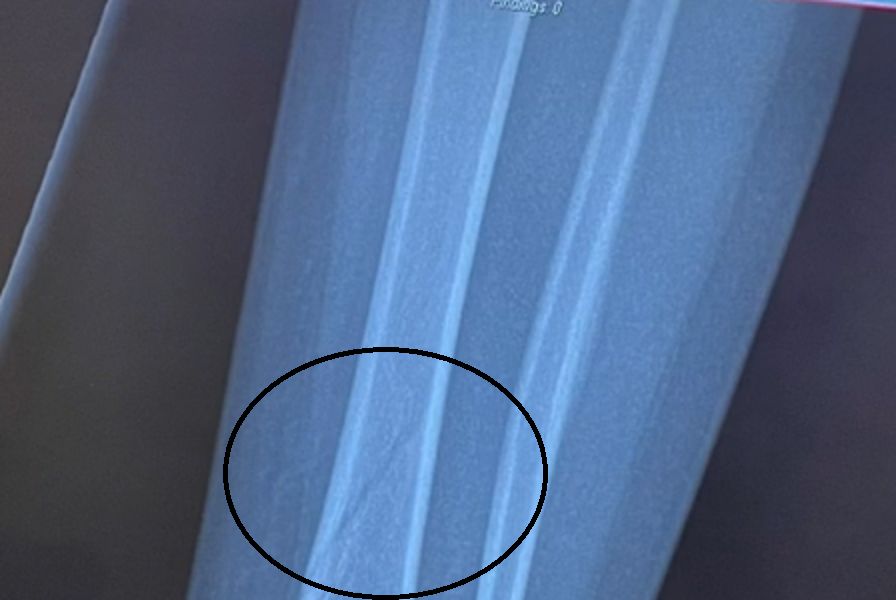

Dopiero następnego dnia, kiedy dziewczynka cały czas się skarżyła na ból w nodze, mama postanowiła zabrać ją do lekarza, by sprawdzić, czy podczas nieszczęśliwego upadku nie doszło do kontuzji. Niestety po wykonaniu prześwietlenia okazało się, że dziewczynka ma złamaną kość piszczelową i strzałkową.

Zdjęcie RTG dwulatki

Zdjęcie RTG dwulatki © TikTok